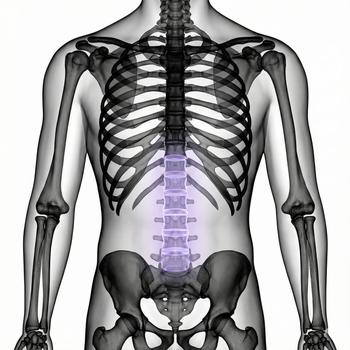

If you have pain in the lower abdomen, irregular bleeding, fertility problems or suspect that something is not right in the lower abdomen, an MRI examination of the pelvis can be the next step to get the right diagnosis. MRI pelvic, also called MRI gynecology, is a painless and radiation-free examination that provides very detailed images of both the uterus, ovaries and fallopian tubes.

The examination is used when other methods such as ultrasound or gynecological examination have not been able to explain your symptoms. With the help of MRI, conditions such as endometriosis, fibroids, cysts, tumors, malformations or effects on nearby organs such as the bladder or intestines can be detected. It is also an important method before fertility treatment or in preparation for surgery.

Whether you are seeking answers to long-term symptoms or following up on previous findings, pelvic MRI gives you and your doctor a clear picture that can form the basis for the right treatment and continued care.